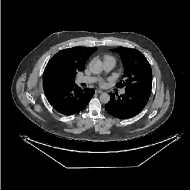

This section compares the reconstruction quality and runtime among the proposed MBIR method, PWLS-ST-, and other three MBIR methods, PWLS-EP, PWLS-DL, and PWLS-ST-. Table I shows that, for both 2D and 3D sparse-view CT reconstructions of the XCAT phantom, the proposed PWLS-ST- model outperforms PWLS-EP and PWLS-ST- in terms of RMSE. In addition, PWLS-ST- using a square transform (of size ) achieves lower RMSE than PWLS-DL using an overcomplete dictionary (of size ) for 2D sparse-view reconstructions. Fig. 3(a) and Fig. 4 show the reconstructed images for 2D and 3D phantom experiments, with different reconstruction models and different number of views. (See the corresponding error maps in the supplement.) The proposed PWLS-ST- consistently gives more accurate image reconstructions compared to other MBIR methods. Specifically, PWLS-ST- has smaller errors in the heart region (see zoom-ins in Fig. 3(a)) of 2D reconstructions than PWLS-DL and PWLS-ST-. In addition, compared to PWLS-ST-, PWLS-DL and PWLS-ST- have some ringing artifacts around the edges with high transition, e.g., edges between air and soft tissues. (See a comparison of profiles of PWLS-ST- and PWLS-ST- in the supplement.) In particular, PWLS-ST- and PWLS-DL give more visible ringing artifacts for 2D reconstruction from fewer views, and PWLS-ST- has these ringing artifacts for 3D reconstructions regardless of the number of views (see zoom-ins in Fig. 4). Table II reports runtimes of different MBIR methods in reconstructing the -views XCAT phantom scan. (FBPConvNet is a non-MBIR method and its runtime for processing a image is approximately one second with a TITAN Xp GPU.) While providing better reconstruction quality, the proposed Algorithm 1 of PWLS-ST- has shorter runtime compared to the algorithms of PWLS-DL and PWLS-ST- in Section III-A. Similar to the PWLS-EP algorithm, the reconstruction time of the PWLS-DL, PWLS-ST-, and PWLS-ST- algorithms can be further reduced by using ordered subsets [51].

Fig. 3(b) shows that when tested on the clinical scan data, the proposed PWLS-ST- method improves reconstruction quality in terms of noise and artifacts removal (e.g., see zoom-ins for soft-issue regions), and edge preservation (e.g., see zoom-ins for bone regions), compared to PWLS-EP and PWLS-ST-. Compared to PWLS-DL, PWLS-ST- achieves comparable image quality, but requires less computational complexity.

The benefit of the proposed PWLS-ST- over PWLS-ST- can be explained when there exist some outliers for some : in (12) gives equal emphasis to all sparse codes – from small to large coefficients that generally correspond to edges in low- and high-contrast regions, respectively – in estimating ; however, PWLS-ST- adjusts to mainly minimize the outliers, i.e., it may not pay enough attention to reconstruct regions with small coefficients. The histogram results in Fig. 1 reveal model mismatch of PWLS-ST- over the iterations. Fig. 3, Fig. 4, and Table I show that PWLS-ST- can moderate model mismatch, and provides more accurate reconstruction than PWLS-ST-.

| (a) 2D fan-beam CT experiments |

| (b) 3D axial cone-beam CT experiments |

III-B3 Generalization Capability Comparisons between a “Denoising” Deep NN and the Proposed PWLS-ST- Method

This section compares the generalization capabilities between the proposed MBIR method, PWLS-ST-, and a denoising deep NN, FBPConvNet [14], that are trained from the phantom data; in particular, we tested the trained PWLS-ST- and FBPConvNet models to phantom and clinical scan data. The results in Fig. 6 show that the non-MBIR FBPConvNet method has higher overfitting risks, compared to the proposed PWLS-ST- MBIR method. When tested on clinical scan data, PWLS-ST- achieves much more accurate reconstruction, compared to FBPConvNet. See Fig. 6(b). When tested on phantom data, FBPConvNet generates more unnatural features as the number of views reduces, although it gives lower RMSE values compared to PWLS-ST-. See zoom-ins in Fig. 6(a). The FBPConvNet results above correspond to those in the recent work [16] that FBPConvNet [14] generated some unexpected structures.